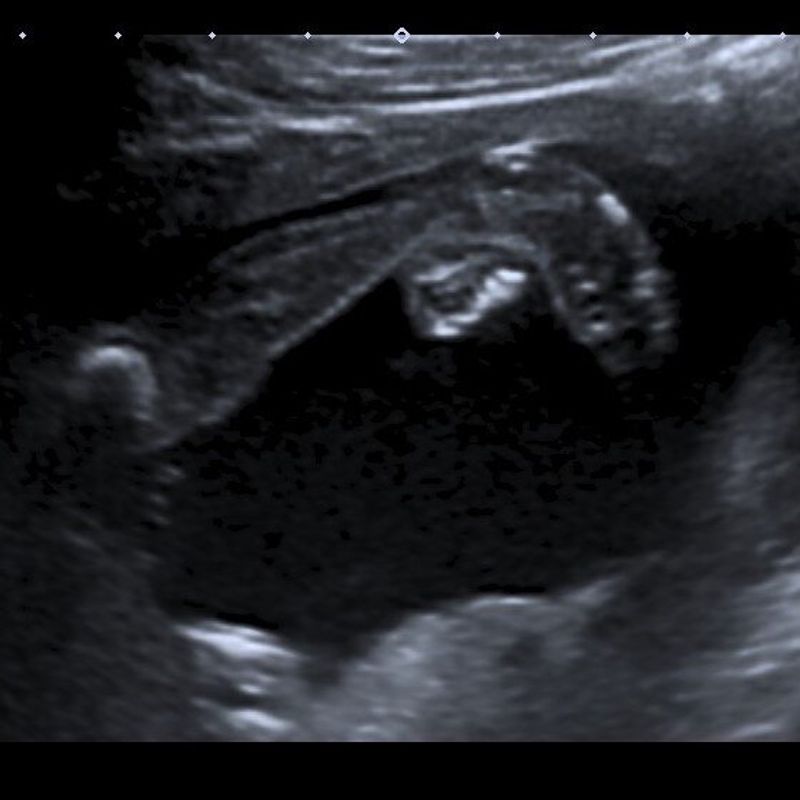

Het is zo ver, vandaag gaan we naar de 20-wekenecho. Ik vind het niet zo spannend, maar ik merk dat mijn vriend wèl gespannen is. Bij mij voelt alles goed en dat zal toch wel een voorteken zijn. Gelukkig hebben wij een goede echoscopiste. Ze heeft jaren onderzoek gedaan, had ze ooit laten vallen. Ze is erg tevreden. Het hartje, de hersenen en de niertjes heeft ze gevonden en deze zien er goed uit. Ik weet eigenlijk niet meer of ze stilviel of dat ze het gelijk vertelde, maar toen ze zei dat onze dochter waarschijnlijk een klompvoetje heeft, werden wij wat stiller. Onze echoscopiste blijft praten en geeft aan dat de andere voet goed is. Ze kan heel duidelijk zien dat de voet goed op de enkel staat. Ze vraagt of we een klompvoetje kennen. Ik zeg ja, meer op de automaat, dan dat ik echt weet wat het inhoudt. Ik heb ervan gehoord, meer eigenlijk niet. Mijn vriend heeft er ook van gehoord, maar kent het eigenlijk ook niet. Ze blijft maar door kletsen en vertelt ons duidelijk dat we ons geen zorgen hoeven te maken. De rest ziet er bij ons meisje zo goed uit, dat ze eigenlijk wel durft te zeggen dat het alleen een klompvoetje is. Het komt straks na de geboorte goed. Het WKZ is hierin in gespecialiseerd. Ze blijft ons een gerust gevoel geven. Ook geeft ze aan dat ze nog niet officieel mag zeggen dat onze meid een klompvoetje heeft. Deze diagnose kan pas echt met zekerheid gesteld worden na de geboorte. Ze stuurt ons daarom ook gelijk door voor een afspraak bij het WKZ. Wij zullen hier een extra echo krijgen. Ook krijgen we meer informatie over kindjes met een klompvoet. Ze zegt nog even gauw voor we de echokamer verlaten: “Ga niet Googlen. Hier kan je van in de war raken en misschien onnodig stressen. Het komt allemaal goed”. Na de echo hebben wij nog een gesprek met één van de verloskundigen van de praktijk. Tijdens dit gesprek krijgen wij de vraag: “Hebben jullie nog vragen over de klompvoet? Hoe voelen jullie je hierbij?“ Nog geen 10 minuten hiervoor hoorden we dat er iets “anders” is met onze dochter en beseffen we dat we geen kennis van klompvoetjes hebben. Dus deze vragen van de verloskundige konden wij beiden niet beantwoorden. We weten niks zeker, en willen gewoon meer weten over wat een klompvoetje precies inhoudt. Het laatste wat je wilt, is dat je kindje ergens last van heeft. Ik ben wat geschrokken, maar tegelijkertijd ook rustig en kalm. Mijn vriend is ook geschrokken en vraagt zich vooral af waarom ik zo kalm ben. Zelf weet ik het ook niet. We lichten gelijk onze ouders in, want ik wil het delen. Ik heb er zelf nog geen idee bij. Tom zijn moeder is kinderarts en heeft jaren op het consultatiebureau gewerkt, misschien weet zij meer. Vandaar dat we al onze ouders bellen.

We nemen onze ouders mee naar de echo. Want ja, zelf maak je overuren in je hoofd en sinds mijn zwangerschap werken mijn hersens heel slecht. Mijn vriend kan gelukkig goed en veel onthouden, maar wij vinden het ook prettig als er meer mensen mee kunnen. In het WKZ worden we goed ontvangen. Ze begrijpen dat er meer mensen mee zijn. Toen mocht dat nog. De vrouw die de echo maakt, is heel rustig en bespreekt alles. Ze geeft duidelijk aan wat ze ziet tijdens de echo. Na de echo gaan we in gesprek met de gynaecoloog. Hij vertelt ons over de klompvoet en het traject. Ook geeft hij ons een website voor informatie en laat hij ons een filmpje zien. Het is vooral een algemeen gesprek, want ook hier wordt duidelijk dat ze de diagnose niet met 100% zekerheid kunnen vaststellen. Dit kan pas op het moment dat onze dochter geboren is. Wat ze wel met zekerheid kunnen zeggen, is dat het gaat om een geïsoleerde afwijking. Dat wil zeggen dat het nergens anders mee te maken heeft, enkel het klompvoetje aan de rechtervoet. Haar hartje, hersenen, maag, nieren en dergelijke zien er perfect uit. Fijn om dat te horen. Met dertig weken mogen we weer terugkomen voor nog een echo en een gesprek op de gipskamer. Het WKZ is één van de 14 klompvoetcentra in Nederland. Prettig, want dit is nog geen 15 minuten rijden van ons huis. We zullen de eerste drie maanden veel naar het ziekenhuis moeten gaan. We krijgen veel informatie, maar toch voelt het goed. We weten dat de kans van genezing ruim 90% is. We kunnen nu weer genieten van de zwangerschap en wachten op de volgende echo.

We hebben de 30-wekenecho. Ondanks dat er vooral gevraagd wordt om alleen naar het ziekenhuis te gaan, gaan we samen. De artsen gaan checken of onze dochter daadwerkelijk echt gezond is en daarom wilt mijn vriend mee. Bij binnenkomst van het ziekenhuis geven ze aan dat we wel met z’n tweeën naar binnen mogen. Wat een opluchting. Uit de echo komt niets bijzonders. We hebben ondanks het klompvoetje een gezonde dochter, geeft ze aan. Nu is het wachten tot de geboorte.